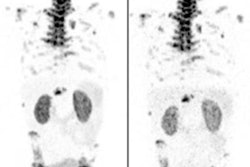

In this trial, Clarity is investigating the diagnostic efficacy of targeted copper-67 (Cu-67) using its SAR-bisPSMA, which targets prostate-specific membrane antigen (PSMA) expressed by prostate tumors, to the prostate cancer tissue samples. Also, it will explore how the images compare with gallium-68 (Ga-68) PSMA-11, which is already approved for use in Australia and the U.S.